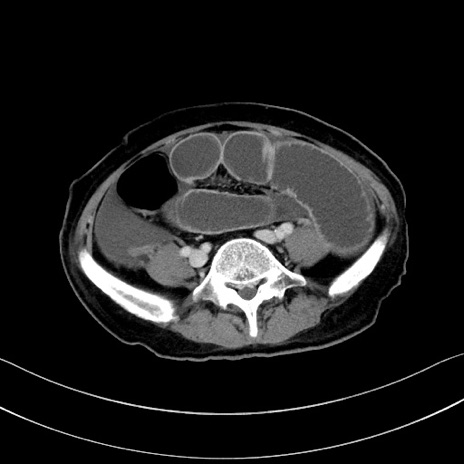

症例28(横断像)

【症例】60歳代男性

【主訴】嘔吐

【現病歴】胃癌にて胃全摘後。食思不振が悪化し、夜中に嘔吐することがある。

【既往歴】胃癌、胃全摘、脾摘、胆摘後

【データ】WBC 5900、CRP 10.56